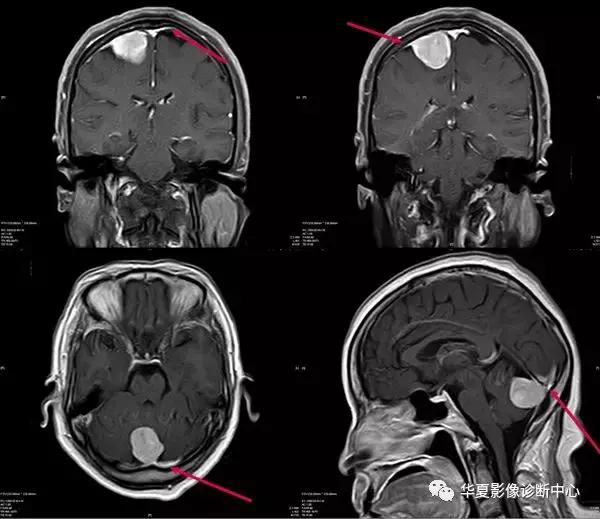

二、硬脑膜尾征:

在增强的MRI或CT图像上,表现为强化并增粗的硬脑膜从肿块延伸出来,长0.5~3cm,形似一条尾巴,称作脑膜尾征或脑膜征,也叫硬膜尾征。硬脑膜尾征是脑膜瘤较常见的增强MRI表现,最初有人提出硬脑膜尾征是来源于肿瘤的直接侵犯,但后来许多研究显示硬脑膜尾很少或没有肿瘤的累及,也有人认为是硬脑膜的反应性改变。目前认为肿瘤侵犯和富血管反应双重机制是产生硬脑膜尾征的原因。脑膜瘤为颅内常见肿瘤,肿瘤起病慢,病程长。典型脑膜瘤多为圆形或类圆形,少数为不规则形,边界清楚锐利。CT平扫大部分表现为均匀高密度15%~20%含钙化,甚至有的完全钙化。25%~30%表现为等密度,常因占位效应或病灶周围水肿而发现。少部分脑膜瘤表现为低密度,多为肿瘤的囊变、坏死所致,少数为胶原纤维化、陈旧性出血或较多的脂肪沉积所致;约10%的脑膜瘤为混合密度,常见瘤周水肿。CT增强扫描除钙化较明显的砂粒型脑膜瘤可能不增强或增强较少外,肿瘤的实质部分往往呈较明显的均匀增强化。

大多数脑膜瘤MRI表现为1WI呈稍低或等信号,T2WI呈稍高或等信号。脑膜瘤内部信号常不均匀,表现为颗粒状、斑点状,这些与肿瘤内血管、钙化、囊变和砂粒体及肿瘤内纤维分隔有关。增强扫描时,脑膜瘤立即发生显著增强并有延迟强化,持续时间达30~60分钟。

确定有没有硬脑膜尾征有3个标准:1)硬脑膜尾巴应该在经过肿瘤的2个连续的断面仁见到;2)硬脑膜尾巴应该从肿瘤向外光滑地逐渐变细;3)硬脑膜尾征应该比肿瘤本身强化更明显。因此,他们认为“硬脑膜尾征”是脑膜瘤高度特异性征象。

尽管很多研究表明“硬脑膜尾征”的出现至少高度提示脑膜瘤的存在,但仍有很多病例报道“硬脑膜尾征”也见于一些非脑膜瘤的肿瘤。比如转移瘤、肉芽肿性脑膜炎(又叫非化脓性脑膜炎,主要包括结核、真菌、嗜酸性肉芽肿、韦氏肉芽肿、肥厚性硬脑膜炎)、血管外皮细胞瘤、淋巴瘤、绿色瘤、胶质母细胞瘤、少突胶质细胞瘤、听神经瘤、乳头状中耳肿瘤、结节病、色素瘤以以及术后改变和放疗等。

关于为什么有些肿瘤会引起硬脑膜尾、有些肿瘤不会有,这个问题从文献上并没有明确的答案。有学者认为脑膜瘤“硬脑膜尾征”的出现有的与肿瘤侵犯有关,有的与富血管反应有关。但这两种解释(即侵袭性浸润和炎性反应)也适用于非脑膜瘤肿瘤出现的“硬脑膜尾征”。但无论怎么解释,“硬脑膜尾征”仍然是提示脑膜瘤的一个有帮助的征象。